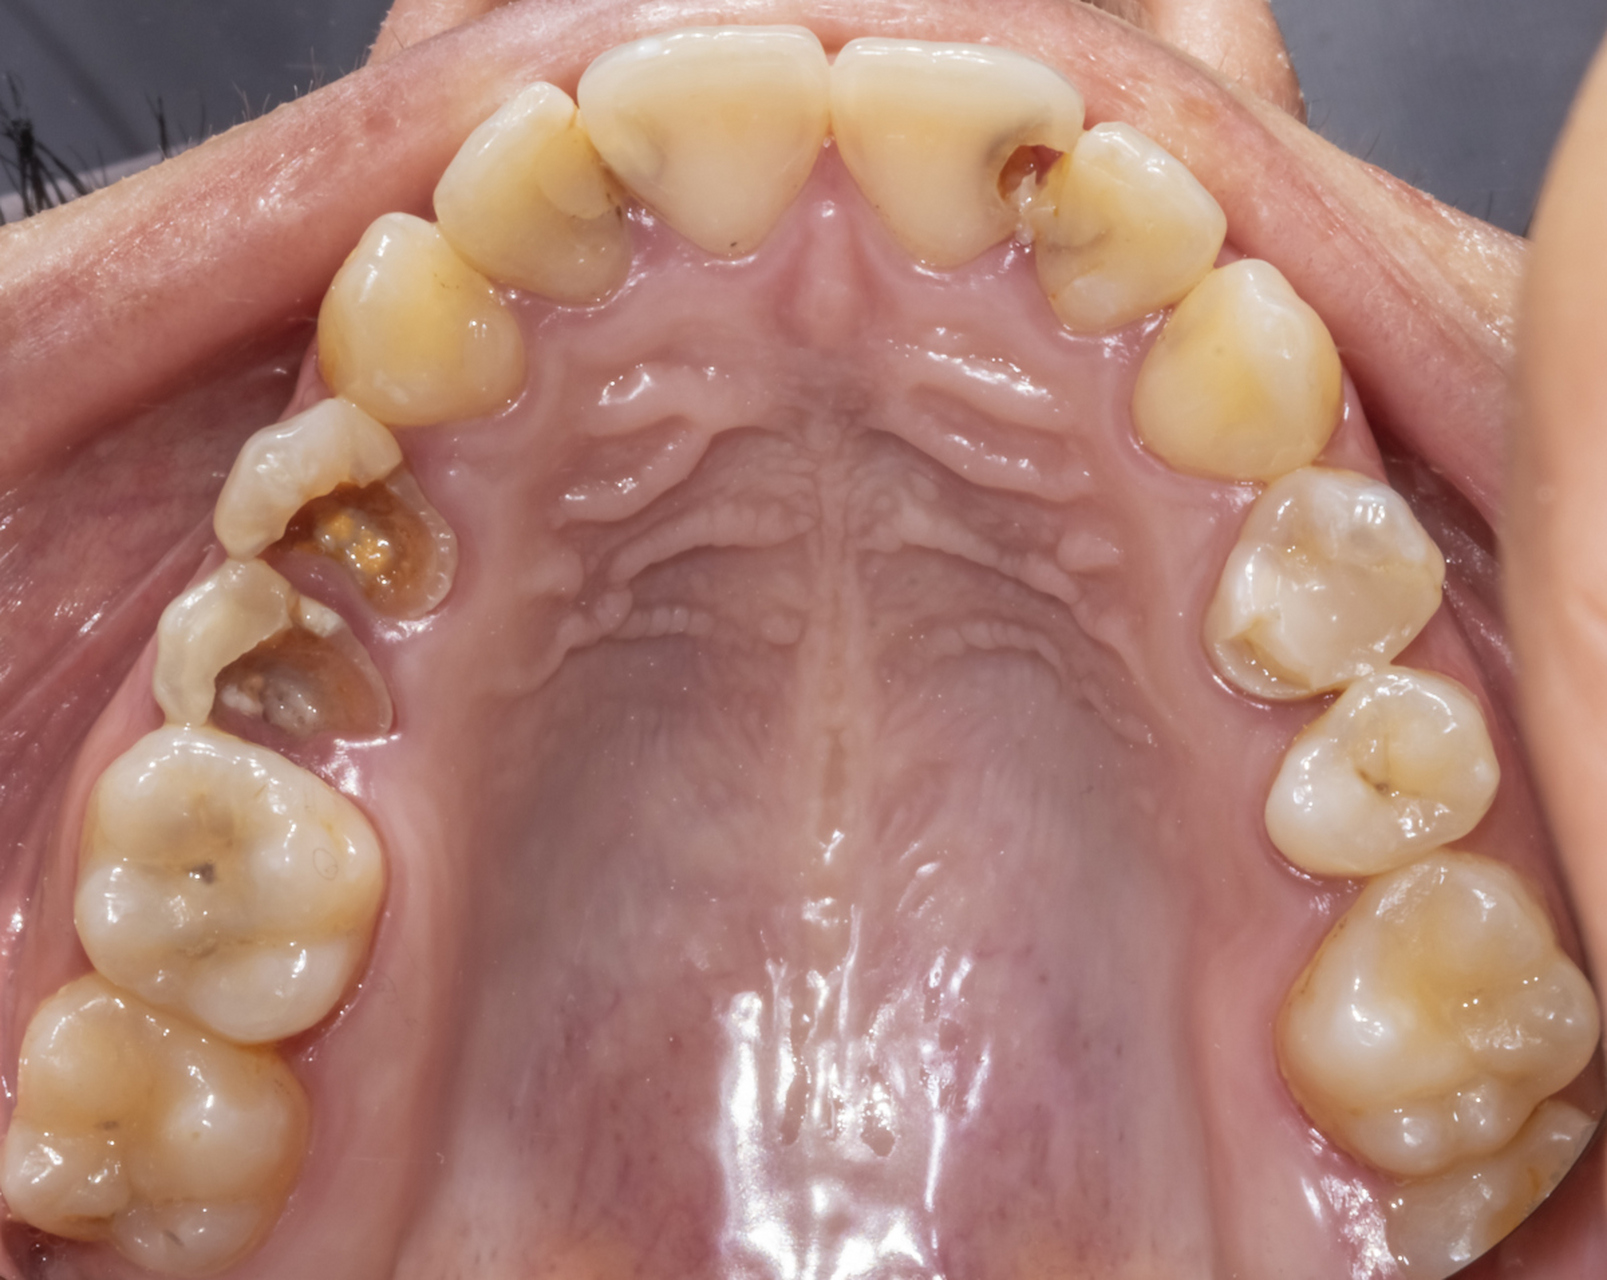

4、龋齿是牙齿硬组织在口腔内多种因素复合作用下发生破损的疾病,也被称为蛀牙或虫牙其诊断需结合色形质三方面特征综合判断从颜色判断,正常牙齿呈现乳白色或珍珠白,而龋齿会导致牙齿颜色发生改变这种改变通常表现为局部脱矿或色素沉积,形成白垩色斑块或黄褐色黑褐色区域例如,早期龋齿可能仅表现;龋齿,实际上是指牙齿上出现的蛀牙,它是牙齿的一种疾病牙齿上出现黑斑点或者黑沟,这就是龋齿的表现形式之一如果发现牙齿上有黑斑或黑沟,那很有可能是龋齿的迹象,需要及时就医如果不及时处理,龋齿会逐渐侵蚀牙齿,导致牙齿损坏,甚至可能引发牙痛等更严重的问题龋齿的发生主要是由于口腔内的;龋齿俗称虫牙蛀牙,是一种细菌性疾病以下是关于龋齿的详细解释一定义与成因 龋齿是由口腔中的细菌,特别是某些产酸菌,作用于牙齿硬组织,导致牙齿无机质脱矿和有机质分解,进而形成龋洞的一种疾病这些细菌通过分解食物残渣中的糖分产生酸性物质,腐蚀牙齿,最终形成龋洞二危害与发展 继发。

5、龋齿是牙齿在细菌等多种因素影响下,牙体硬组织发生的慢性进行性破坏性疾病其发生机制与细菌活动密切相关口腔中的细菌会黏附在牙齿表面,形成牙菌斑牙菌斑内的细菌能分解食物残渣中的糖类,产生酸性物质牙齿的主要成分是矿物质,这些酸性物质会逐渐腐蚀牙齿表面的牙釉质,导致牙釉质脱矿,进而形成。